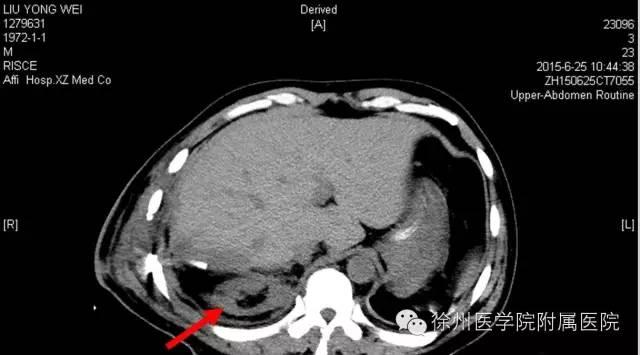

该声明称,患者手术时间是2015年6月20日,术后分别于2015年6月21日(术后第1天)和6月25日(术后第5天)的2次CT复查均显示该患者的右肾存在。

该声明还专门张贴了两张CT复查图。

图二 2015年6月25日(术后第5天)CT,右肾如箭头所示。